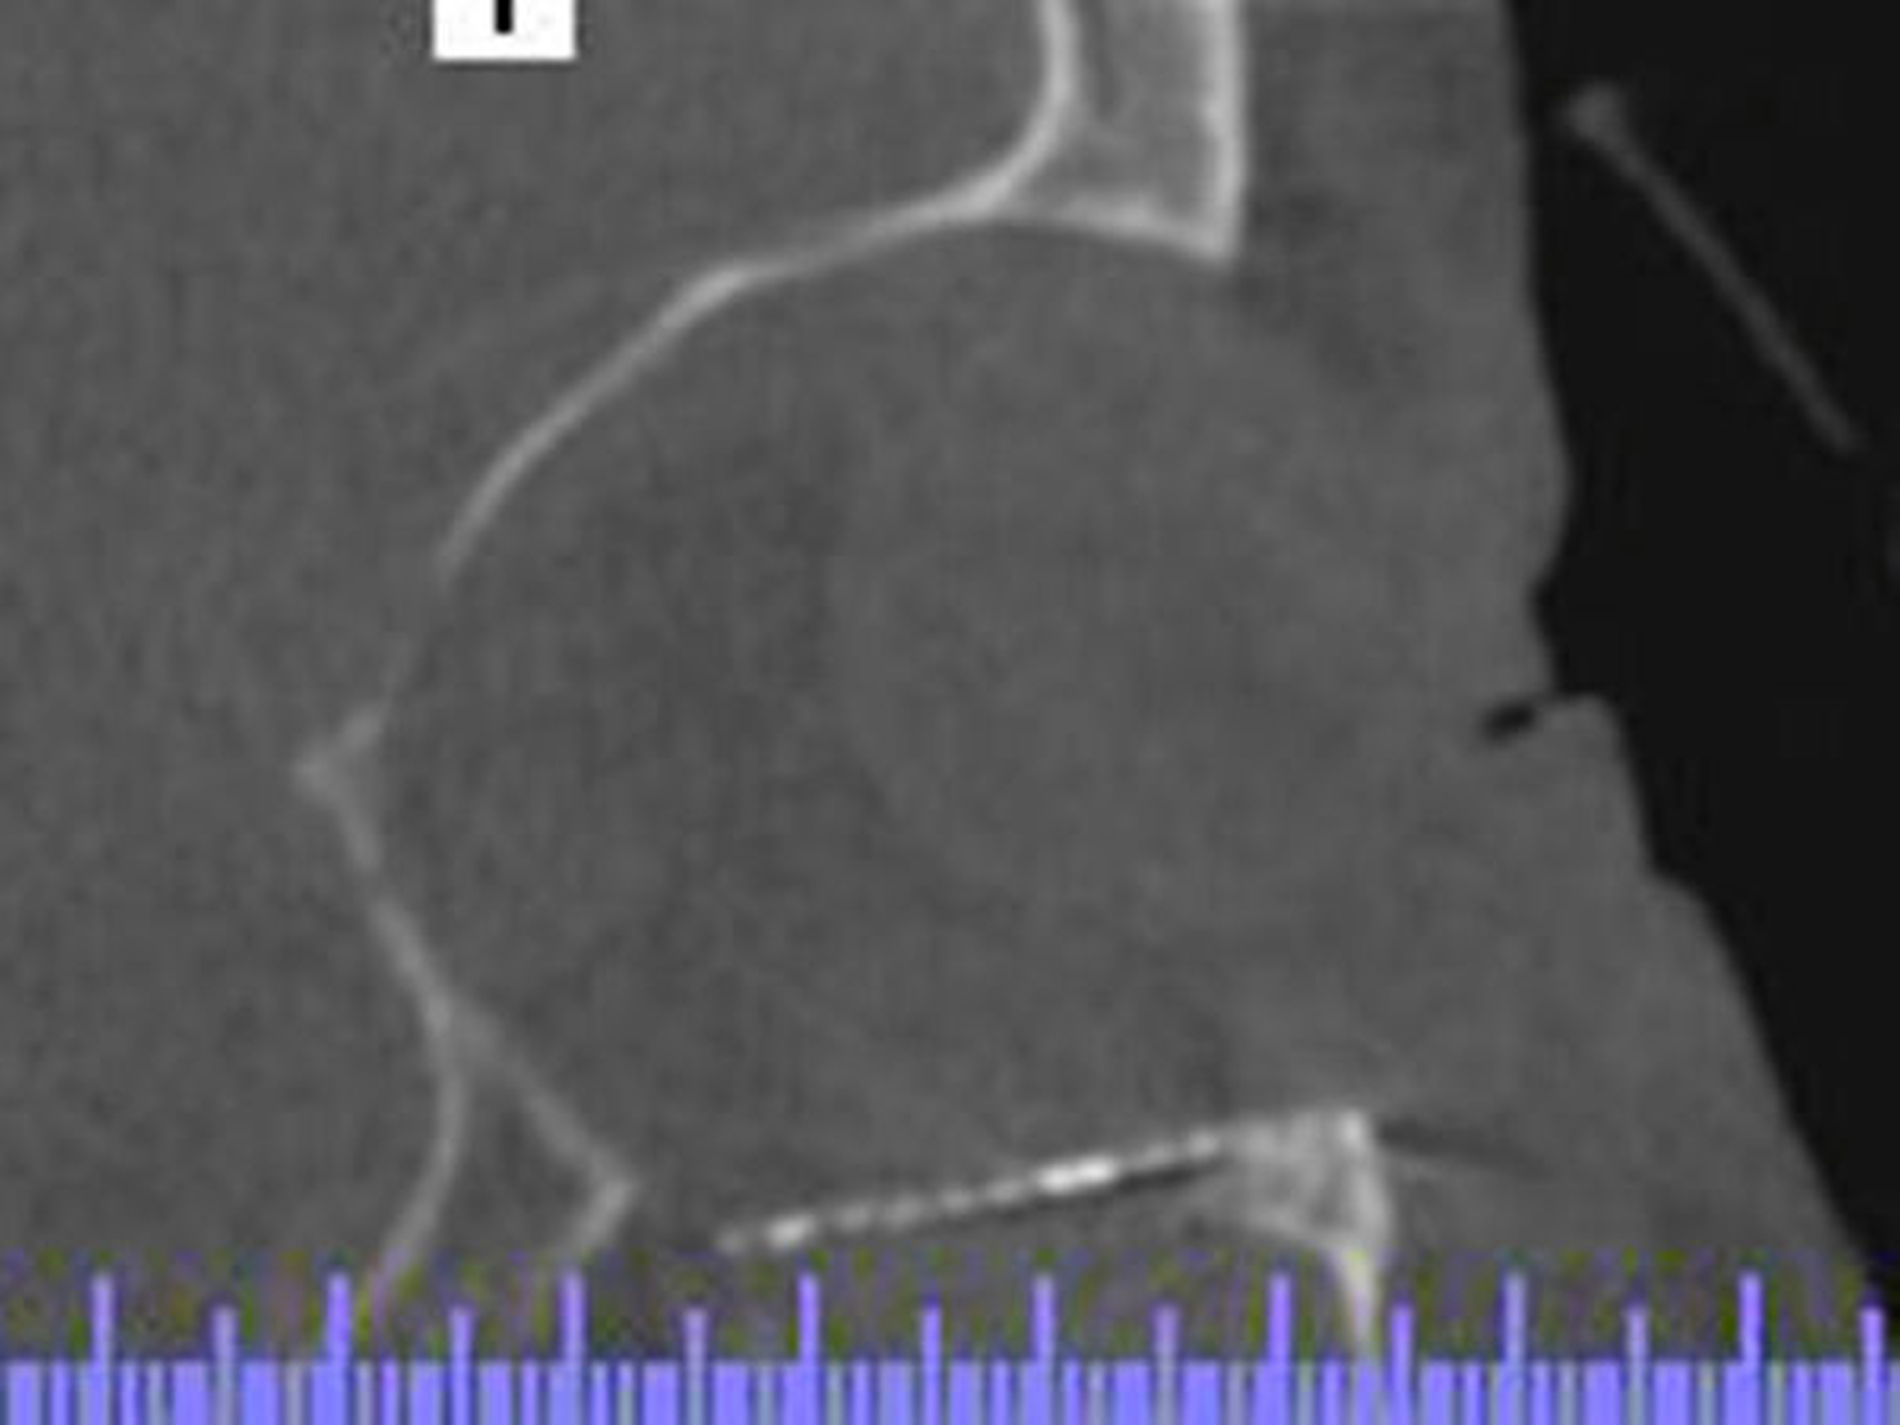

Nach dem Notfalleingriff mit Weichgewebsversorgung der infraorbitalen Wunde wurde eine Orbita-CT zur Kontrolle und zum Ausschluss eines retrobulbären Hämatoms sowie einer Bulbusperforation durchgeführt. Der Bulbus stellte sich rund und normal dar, ohne Hinweise auf eine Perforation der Bulbuswand. Der Nervus opticus zeigte sich intakt. Es waren keine Anzeichen einer Herniation der Augenmuskulatur bei Orbitabodenfraktur zu sehen.

Nach Abschwellung wurde am dritten Tag nach Traumas der Orbitaboden in Intubationsnarkose reponiert und mittels Titan-Mesh rekonstruiert. Der Nervus infraorbitalis rechts konnte gut dargestellt und komplett entlastet werden. Im Anschluss in der gleichen Narkose wurden die Tränenwege durch die Kollegen der Augenklinik geschient.